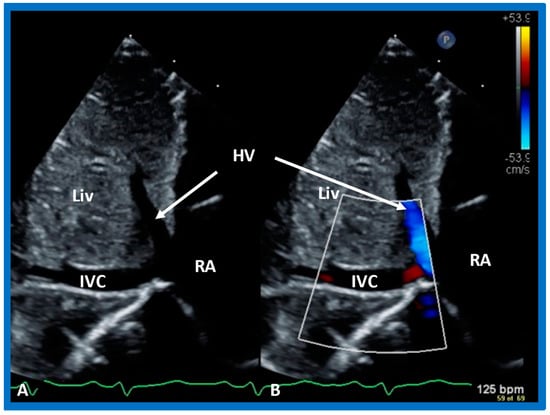

5.2.5. Venoatrial Concordance

During embryonic development, the IVC is connected to the sinus venosus, which later (post-natal) becomes the RA. Consequently, the side of the IVC determines the location of the RA. Therefore, the IVC is on the right side in subjects with situs solitus, while the IVC is on the left side in subjects with situs inversus. The position of the IVC can easily be defined by echo imaging in the subcostal view (Figure 27). The absence of IVC entrance into the right atrium in subjects with interrupted IVC (infrahepatic) with azygos or hemiazygos can also be shown in careful subcostal echo studies.

Figure 27. Subcostal echo images in two-dimensional (A) and color flow (B) illustrate the entrance of the inferior vena cava (IVC) into the right atrium (RA). HV, hepatic vein; Liv, liver.

More invasive techniques, such as nuclear angiography or cardiac catheterization (Figure 28), may also define the atrial situs but are not required for the sole purpose of atrial situs determination. In subjects who have infrahepatic interruption of the IVC with either azygos or hemiazygos continuation, the position of the azygos vein is not useful in determining the atrial situs.